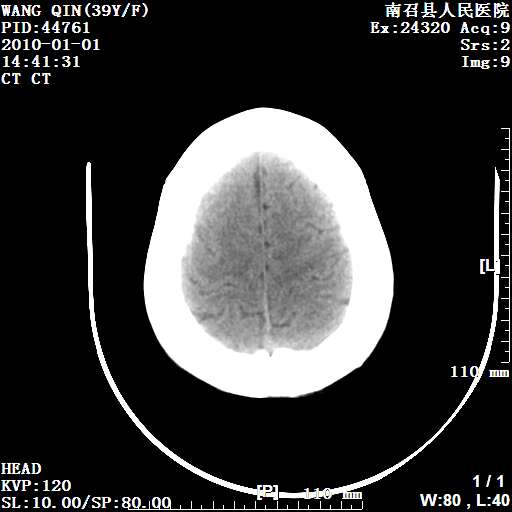

以下是引用随光逐影在2010-1-22 9:03:00的发言:[br]考虑左侧中颅窝(蝶骨翼区)脑膜瘤侵犯蝶骨翼并突入左侧眼眶。

以下是引用水过无痕在2010-1-22 14:55:00的发言:[br]一、定位:颅外占位;二、定性:恶性可能性大;三、组织来源:来源于左侧眼外直肌或其他部位;考虑为:横纹肌肉瘤>转移瘤>脑膜瘤.